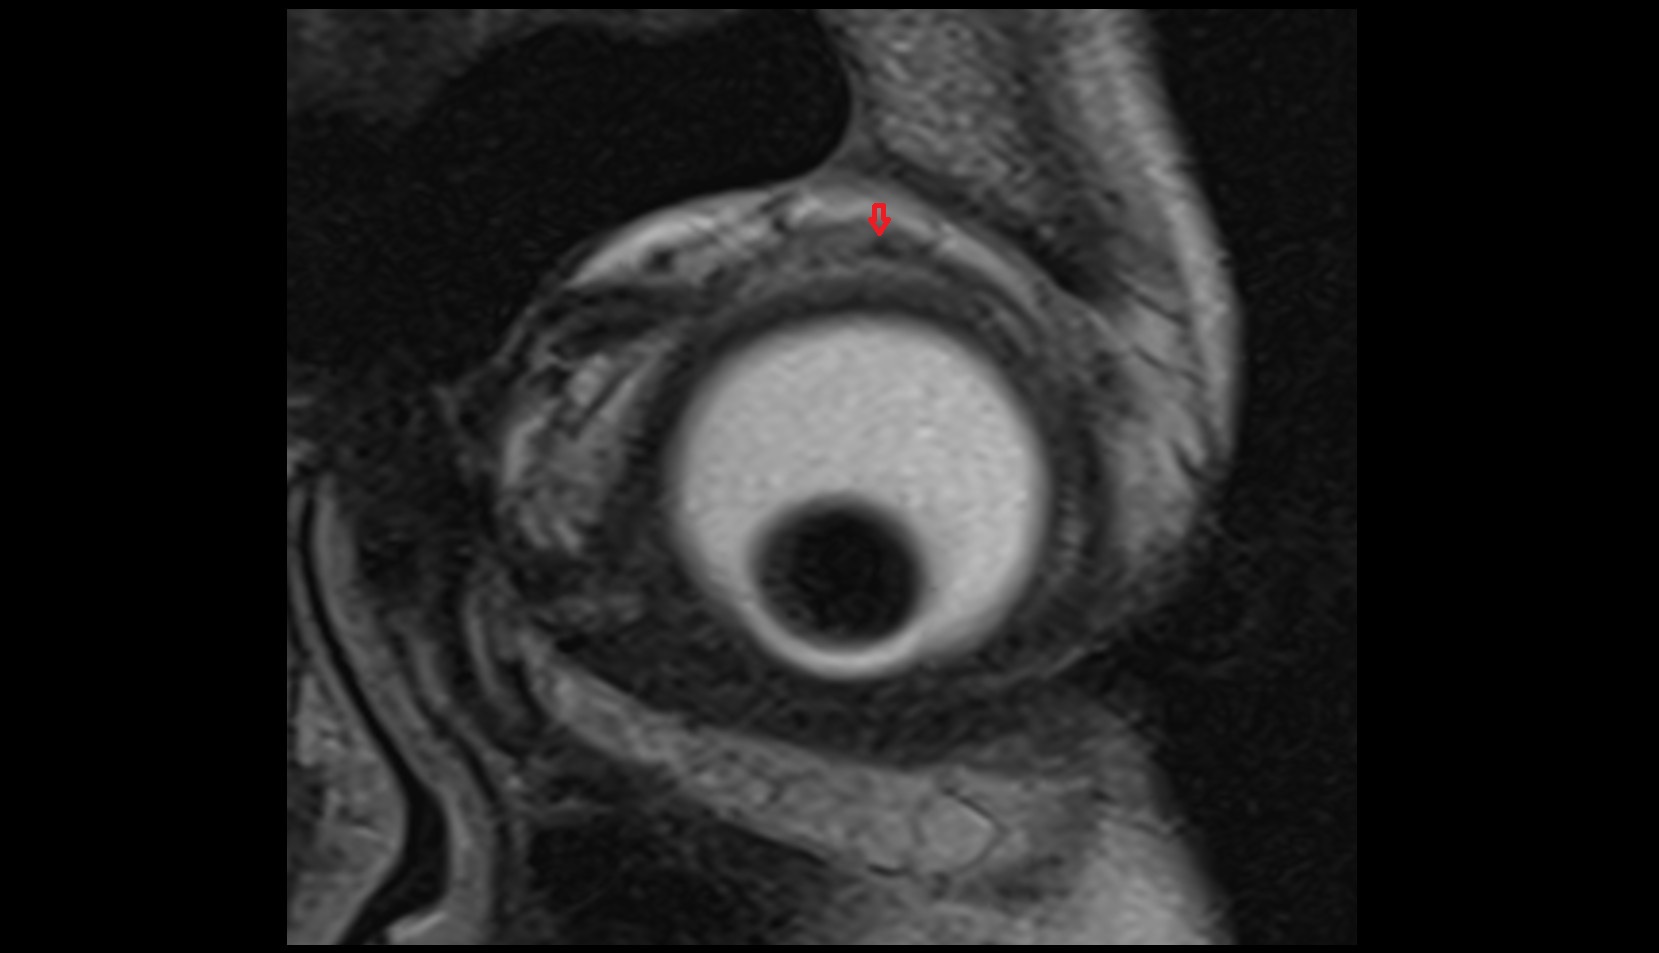

- Uterus

- Endometrium of uterus

- Myometrium of uterus

- Junctional zone of uterus